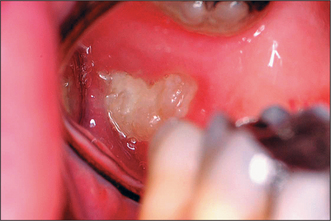

Most patients attending hospital with impacted teeth are referred because of pain and infection, associated with partially erupted teeth (Fig. 5.2); however, many impacted or displaced teeth are unerupted and asymptomatic and therefore an incidental finding following radiographic examination. Occasionally, unerupted wisdom teeth, in the absence of any obvious infection, can give rise to discomfort (often described by patients as ‘pressure’ at the back of the mouth). It is important to exclude other possible causes such as temporomandibular joint pain and pulpitis/periapical abscess from another tooth.

image

Fig. 5.2 Pericoronitis affecting a partially erupted wisdom tooth. Note the soft-tissue erythema.

Intraoral anatomical factors that may influence surgical access include size of the tongue and degree of mandibular opening. The position of the impacted wisdom tooth should be noted (unerupted, partially erupted or erupted but non-functional), together with any signs of infection (e.g. caries, pericoronitis). Probing the distal aspect of the second molar will confirm whether the buried tooth is in communication with the mouth.